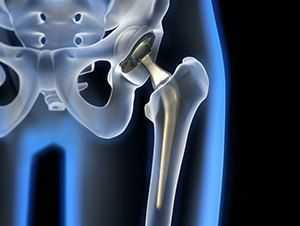

Изображение положения эндопротеза в теле человека.

Операция по установке протеза ТБС является единственным методом, который «ставит» пациента на ноги, избавляет от изнурительных болей и ограниченной трудоспособности, позволяет вернуться к здоровой физической активности. Неприятные патологические ситуации, связанные с имплантацией, возникают нечасто, о чем должен быть проинформирован пациент. Согласно проводимым рандомизированным контролируемым исследованиям, получены следующие данные:

Если не лечить

Асептический некроз головки тазобедренного сустава - тяжелая патология, которая сама не разрешится. Если оставить ситуацию без должного внимания, заболевание может привести к инвалидизации. В одном случае может развиться вторичный коксартроз, требующий замены сустава на протез (эндопротезирование тазобедренного сустава). Во время операции удаляется головка тазобедренного сустава вместе с частью бедренной кости и на их место ставится протез.

Замена сустава позволяет рассчитывать на благоприятный прогноз. Протез позволяет полностью восстановить утраченные функции.